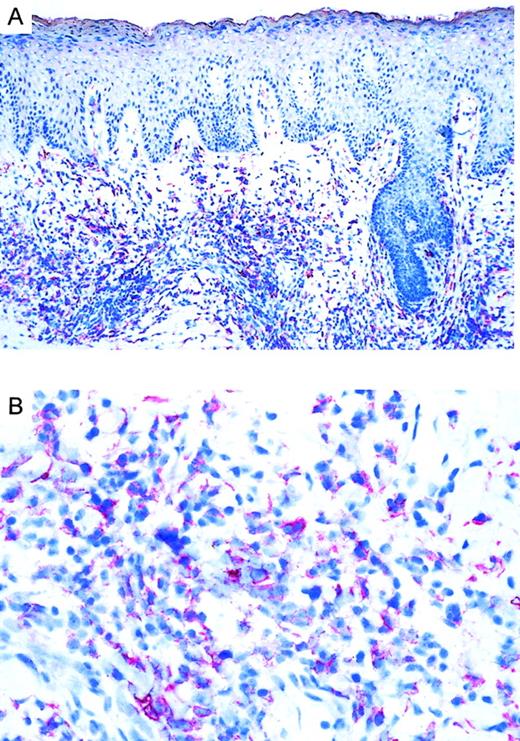

Twenty CTCLs, consisting of 8 CD30+ large-cell lymphoma, 6 mycosis fungoides, and 6 Sézary syndrome patient samples, were analyzed by immunohistochemistry. CD30 was expressed in all large-cell CTCLs (Table 1). Variation in the admixture of inflammatory cells accounted for the difference in numbers of CD30+ cells in the infiltrate. Staining for the chemokine receptor CCR3 demonstrated expression of CCR3 in 7 of 8 CD30+ CTCLs investigated (Table 1; Figure1). No epidermotropism of CCR-3+ cells was observed. There was faint staining of keratinocytes, which is explained by the recently described CCR3 expression on these cells.21 Mycosis fungoides (n = 6) and Sézary syndrome (n = 6) sections were CD30−except one case (no. 17) where few CD30+ cells were detected. In CD30− CTCL, there were always fewer than 5% of cells positive for CCR-3. In most cases, the extent of CD30 expression corresponded to the expression of CCR3 (Table 1). CCR4 expression was found in 4 of 8 CD30+ CTCLs as well as 1 of 6 MF cases and 1 of 6 Sézary syndrome cases. No CCR8 staining was observed in any of the samples.

Immunoreactivity of CCR3 in CTCL.

(A) CCR3 immunoreactivity in cryosections of a CD30+large-cell CTCL (no. 7) with the use of the alkaline phosphatase/anti–alkaline phosphatase method. Original magnification, × 100. (B) CCR3 immunoreactivity in cryosection of a CD30+ large-cell CTCL (no. 7) with the use of the alkaline phosphatase/anti–alkaline phosphatase method. Original magnification, × 400.

CTCLs are a group of lymphoproliferative disorders with clonal expansion of transformed T cells in skin.25 Surface expression of CD30 distinguishes a subtype of large-cell CTCL with slow progression, indolent behavior, and favorable prognosis.26-29 CD30 is a member of the tumor necrosis factor receptor family, which was originally described as Ki-1 antigen on Hodgkin and Reed-Sternberg cells in Hodgkin disease.30,31 The favorable prognosis of CTCL may be related in part to the fact that dissemination to other body compartments occurs only late during disease development. This might be suggestive of chemotactic forces that keep lymphoma cells confined to the skin. The insight into the field of chemokine/chemokine receptor interactions has been developing rapidly.32 Recently, chemokine receptor expression has been correlated with differential recruitment of polarized Th-1 or Th-2 T cells as well as secretion of Th-1 or Th-2 cytokines.33-37 It has been shown that CCR3 is preferentially expressed in vitro by Th-2 cells.33,35 In this context, the presence of eosinophils as well as expression of Th-2 cytokine mRNA in lesions of CD30+ cutaneous lymphomas is of interest.24 We reasoned that recruitment of CD30+ Th-2–like lymphoma cells might be mediated by the presence of CCR3 ligands in skin in association with constitutive expression of CCR3 on lymphoma cells. The availability of a monoclonal antibody to CCR3 allowed us to perform the present study.38 Seven of 8 CD30+ CTCLs demonstrated expression of CCR3 on lesional tumor cells (Table 1; Figure 1). This finding was confirmed by flow cytometric staining of tumor cell suspensions (Figure 2). Interestingly, there was high expression of CCR3 on lymphoma cells, comparable to the expression on eosinophils, which was also reflected by strong staining intensity for CCR3 with the use of immunohistochemistry (Figure 1). CD30− CTCL samples did not express CCR3 in spite of a suggested Th-2 differentiation of tumor cells.39,40However, there is also recent evidence that Th-2 cytokine mRNA might be absent in CD30− CTCL.41 The question of chemokine redundancy must be addressed early in any discussion of the potential role of chemokines in disease. There might be an enormous overlap in ligand-receptor specificity. Even though eotaxin/CCL11 has a very specific binding to CCR3, other chemokine receptors, such as the skin-associated chemokine receptor CCR4, might play a role in the homing of lymphoma cells to skin. In our study, 4 of 8 CD30+ CTCLs, 1 of 6 Mycosis fungoides cases, and 1 of 6 Sézary syndrome samples expressed CCR4. Significant CCR8 expression was absent in our samples. In most cases, temporal and spatial patterns of chemokine receptor expression are connected with ligand-receptor specificity to result in a disease-specific pathology.42 An important question is the demonstration of a functional chemokine receptor expressed on skin-infiltrating lymphoma cells. Most studies have demonstrated the presence of chemokines or their receptors in situ but have failed to provide data on fresh tumor cell suspensions. One recent investigation demonstrated differentially expressed chemokine receptors CCR3 and CCR5 on infiltrating leukocytes but not neoplastic cells in Hodgkin disease lymph nodes.43 We were able to demonstrate receptor functionality on CD30+ tumor cells with an assay used in studies of CXCR4/SDF1-α interactions.22 In the presence of the CCR3 ligand eotaxin/CCL11, specific partial down-regulation of CCR3 in tumor cell suspensions was observed (Figure 3A).